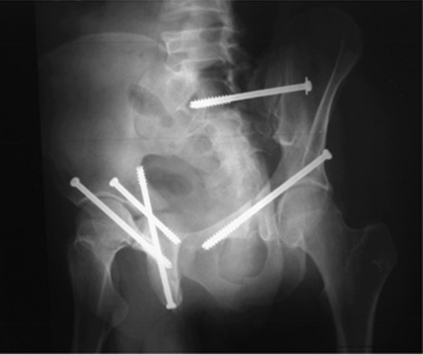

Seven bone corridors — fluoroscopic views

Fluoroscopic views.